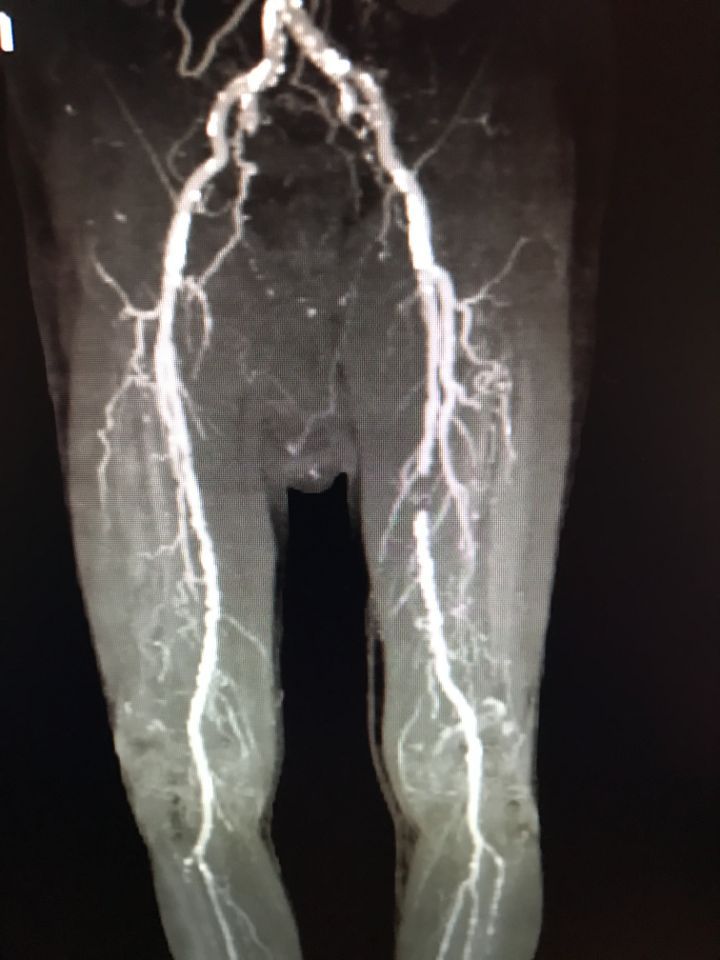

Ecco alcune immagini degli interventi eseguiti dal Dottor Viglione presso il suo studio a Cuneo.